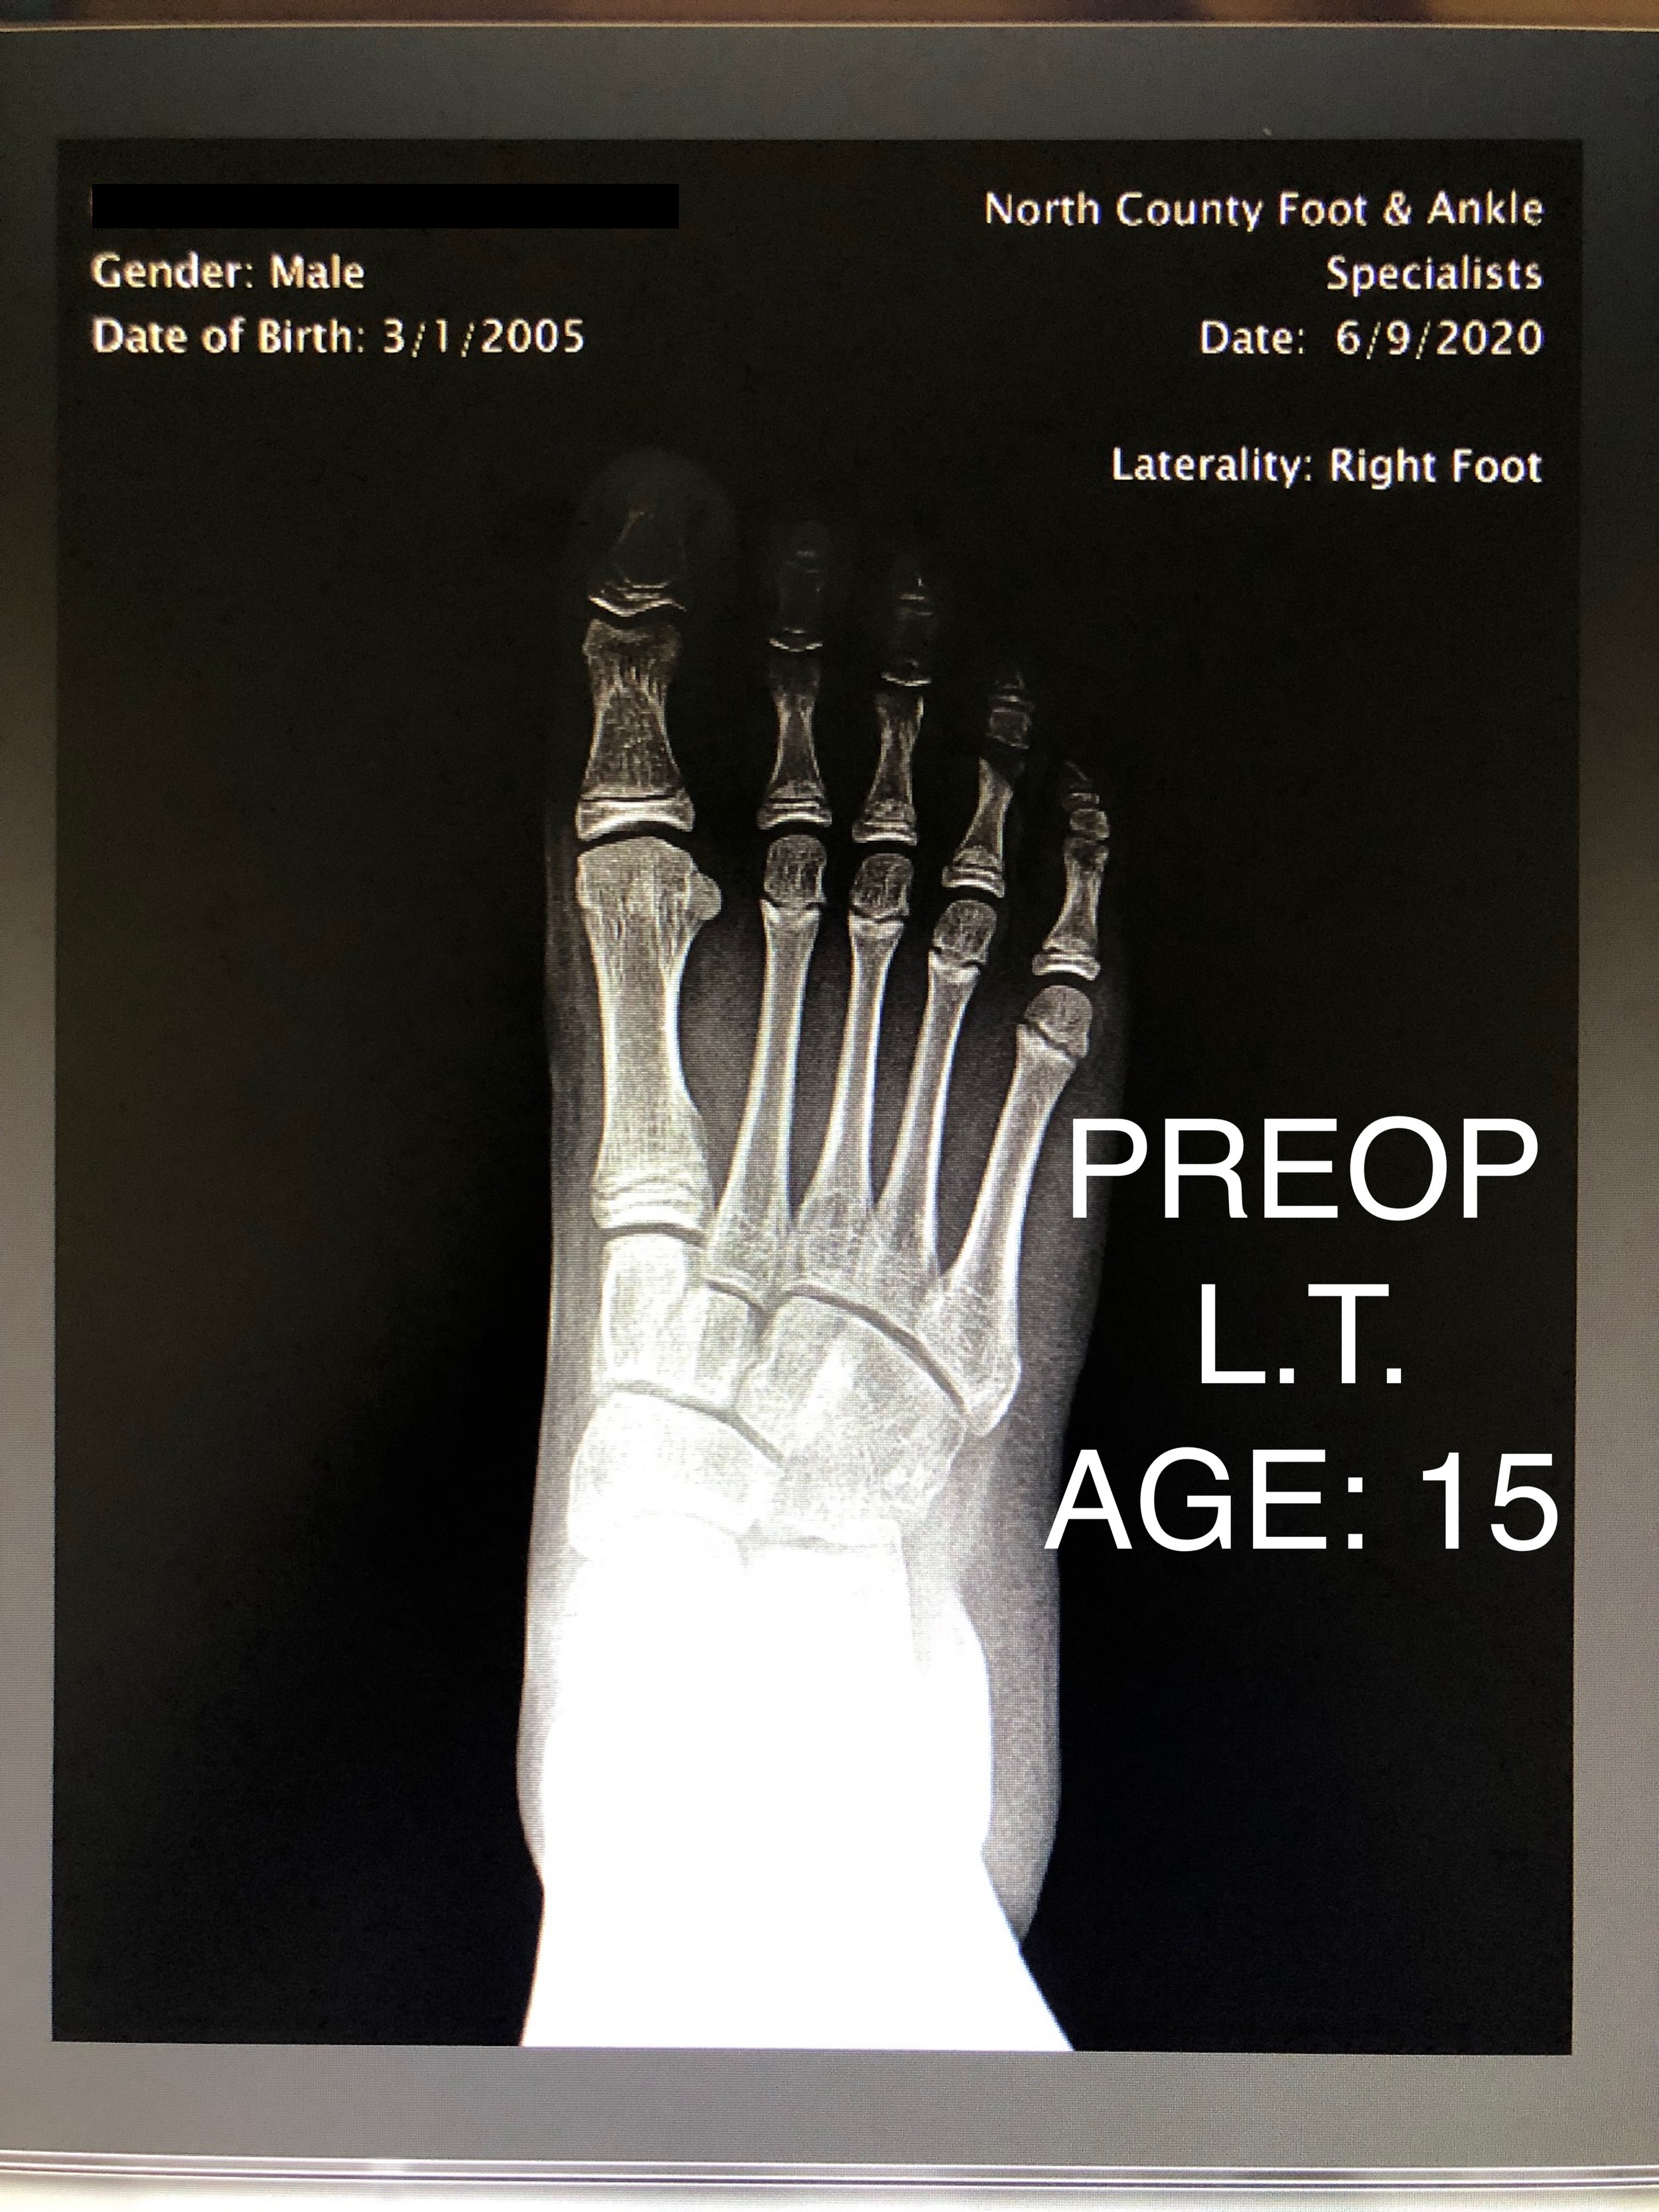

PEDIATRIC FLAT FOOT